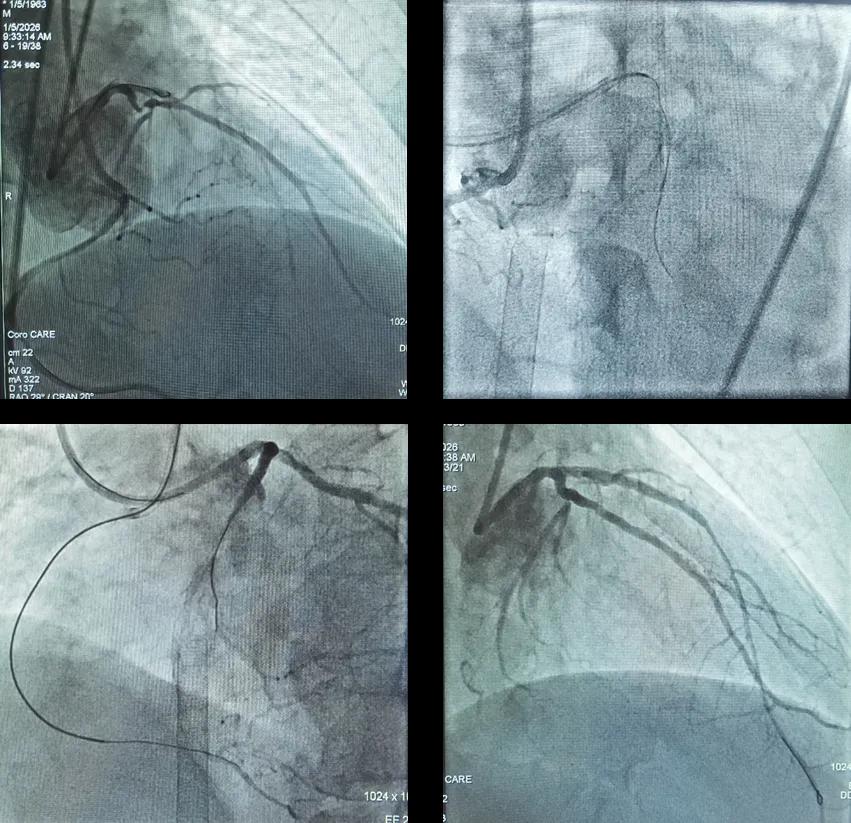

63岁的杜先生因“咽部紧缩感6个月,加重20天”入院。这个看似普通的症状背后,隐藏着一颗正在衰竭的心脏。 在心内一科,他被确诊为急性非ST段抬高型心肌梗死、慢性心力衰竭急性加重。患者心脏明显扩大,进一步的检查...